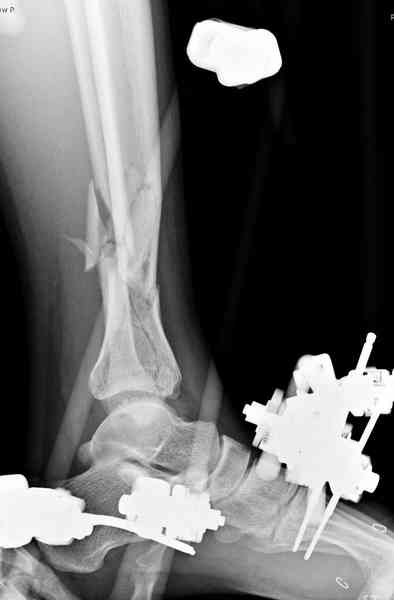

При высокоскоростных переломах редко можно встретить изолированную травму пилона, и в моей практике изолированные травмы большая редкость, поэтому, как дополнение к обсуждаемой теме, решил представить свежий, двухдневной давности случай.

Предыдущей сменой до 4:00 утра по поводу открытого перелома бедра, тибиал плато, пилон и надколенника сделана операция.

Пострадавшему 21 г., травма скоростная, после I&D с расширением раны, на бедре сделана операция ретроградным интрамедуллярным штифтом, остеосинтез с частичной резекцией надколенника и ушивание собственной связки.

На голень наружный фиксатор, рану на бедре ушили (рана была изнутри кнаружи всего 2 см). По протоколу травматических больных, до операции обследован ангиографически, (у больного дистально не смогли определить пульсацию) сосудистый хирург подтвердил проходимость на всем протяжении магистрального сосуда нижней конечности по снимкам ангиограмм.